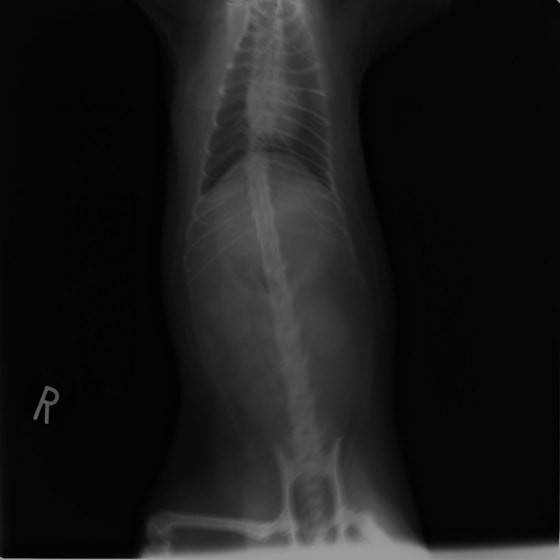

9歳 チワワ 4.8kg

主訴:2日前の夜に桃の種を飲み込んだとのこと。元気・食欲に問題はなく、嘔吐などの消化器症状もみられなかった。誤飲した当日に他院にて催吐処置を試みたが、吐き戻さなかったとのこと。

単純レントゲン検査:明らかな異常所見なし

消化管バリウム造影レントゲン検査:胃内にて異物の存在を疑う異常所見を認めた。

造影直後

内視鏡検査:内視鏡下にて、バスケット鉗子を用いて胃内異物を摘出。

異物内容:桃の種 (約4cm大 写真上)、とうもろこしの芯 (約2.5cm大 写真下)

本症例は、床に落としてしまった桃の種を誤飲していました。動物の体格に対して異物が非常に大きく、開腹手術となる可能性があった症例でした。また、桃の種と一緒に出てきたとうもろこしの芯は、日々のおやつとして与えていたものということでした。とうもろこしの芯は非常に硬く、小さく切って与えても消化されず、長期間胃内に残ってしまうことや腸閉塞の原因となる為、注意が必要です。